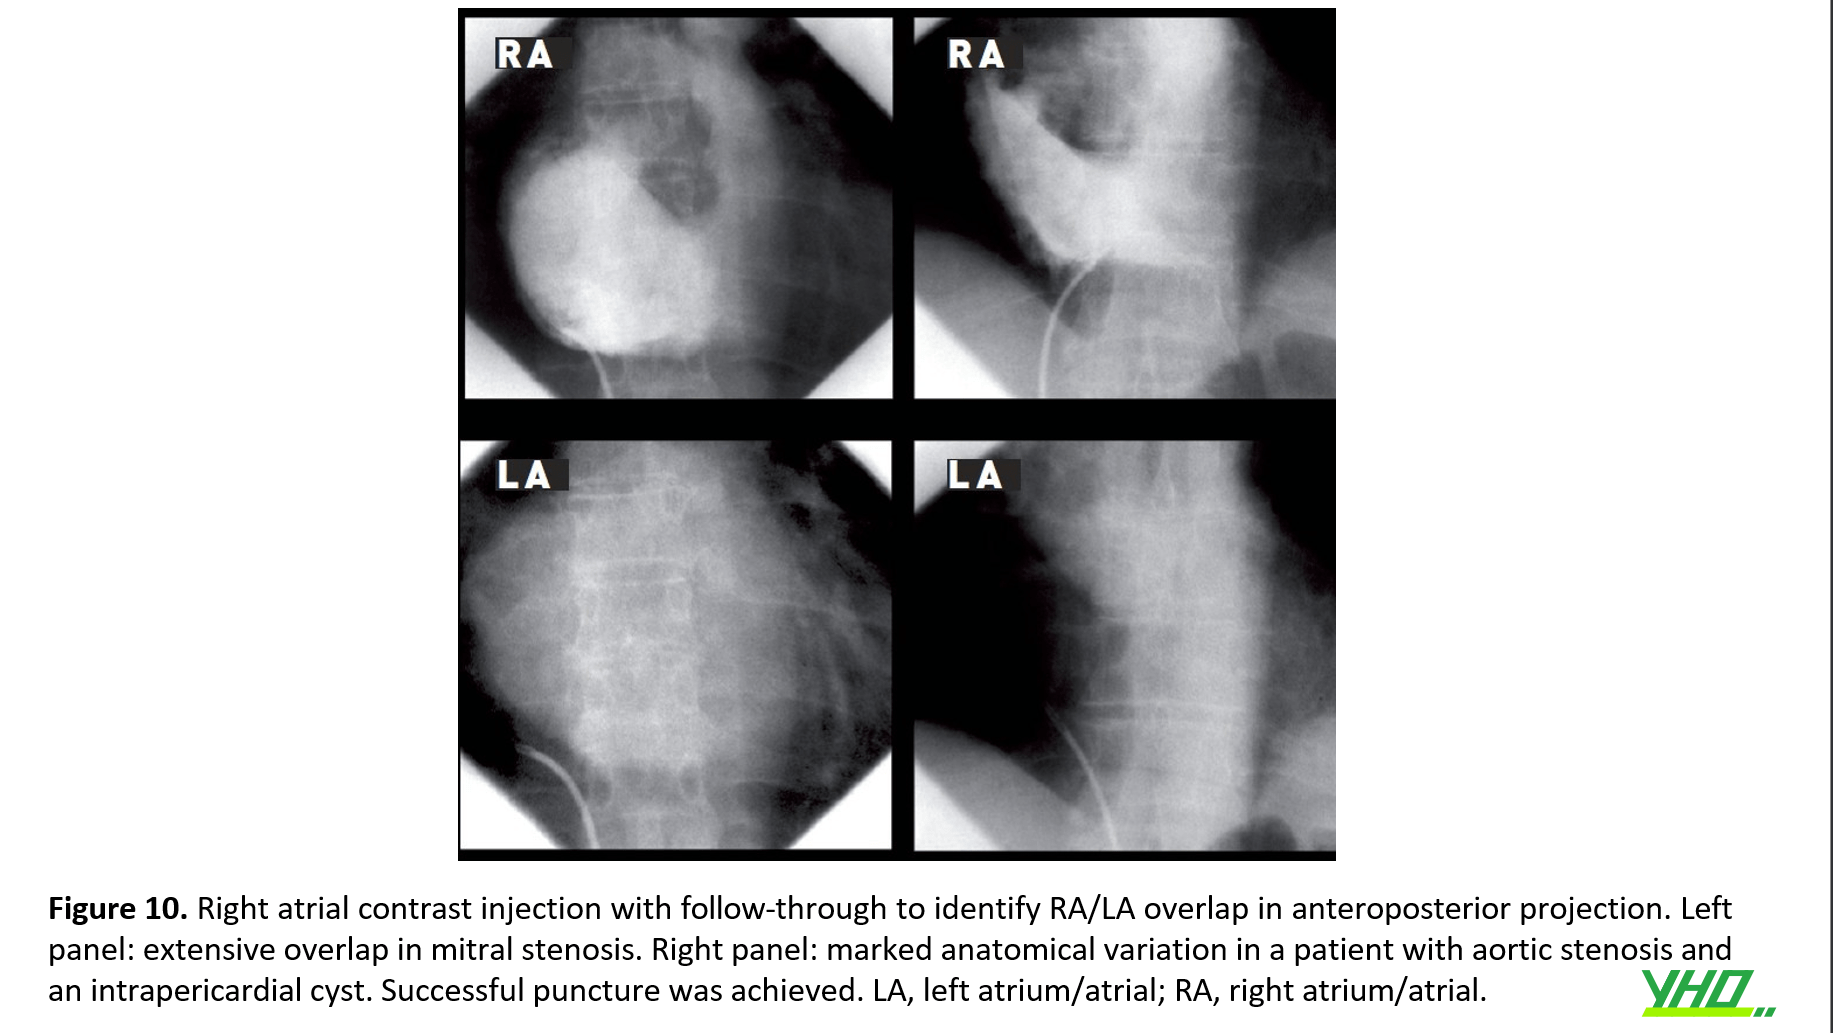

Tiêm chất cản quang (ví dụ 30 mL với tốc độ 12 mL/s) vào RA với hình ảnh theo dõi đến LA cho phép xác định được vùng chồng lấp của hai khoang tâm nhĩ. Ở vị trí trước sau, điều này có thể được xác định dựa vào các đốt sống. Nhiều thủ thuật viên sử dụng điều này để xác định vị trí chọc, đặc biệt khi giải phẫu trong tim bị biến dạng. (hình 10)